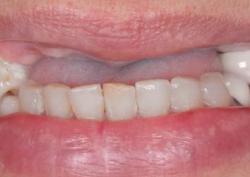

Галина, 68 лет

Жалобы пациента:

Полное отсутствие зубов на верхней челюсти затрудняли пережёвывание пищи, из-за чего была вынуждена перейти на мягкую и протёртую еду. Также она испытывала психологический дискомфорт — стеснялась разговаривать и улыбаться, так как старый съёмный протез плохо фиксировался и выглядел неестественно.

Что делали:

Результат:

Пациентка снова может свободно есть любимые продукты, включая твёрдые фрукты и мясо. Исчезли проблемы с дикцией.